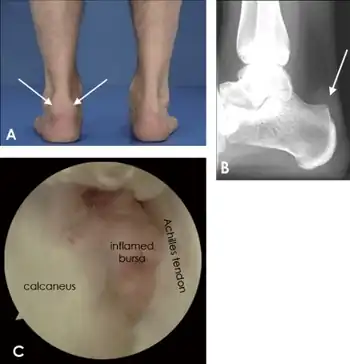

| Preoperative X-ray ankle joint lateral view showing (a) the parallel pitch lines (PPLs) determine the prominence of the bony projection. (b) Ultrasound ankle showing Achilles tendon, tetrocalcaneal bursa, and calcaneum | |

Retrocalcaneal bursitis is an inflammation of the bursa located between the calcaneus and the anterior surface of the Achilles tendon.[1] It commonly occurs in association with rheumatoid arthritis, spondyloarthropathies, gout, and trauma.

The pain is usually on the back of the heel and swelling appears on lateral or medial side of the tendon.